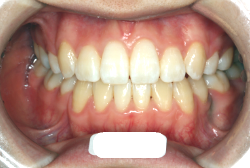

検査の結果、乳歯の下には後継ぎの永久歯が先天的に欠如していました。配列の凸凹が厳しく非抜歯で矯正することは難しく、仮に無理をして非抜歯治療をしても後々「後戻り」が懸念されることから、このような症例の場合は通常、上下顎左右第一小臼歯を抜歯させていただくのですが、左下は乳歯を抜歯して、第一小臼歯は残すことにしました。これで結果として、小臼歯部を上下左右で一つずつ減らしたのと同じ状況になります。治療後は歯並びが綺麗になっただけでなく、噛み合わせ的にも正しい状態が確立しています。

このように、先天的に永久歯が足りないという症例は最近増えています。親知らずはなくても特に問題になりませんが、その他の歯が足りないと言うのは審美的にも機能的にも重大な障害となります。しかし、矯正治療を正しく行えば、結果として歯がすべてあった場合と全く同じ仕上げにすることも可能です。